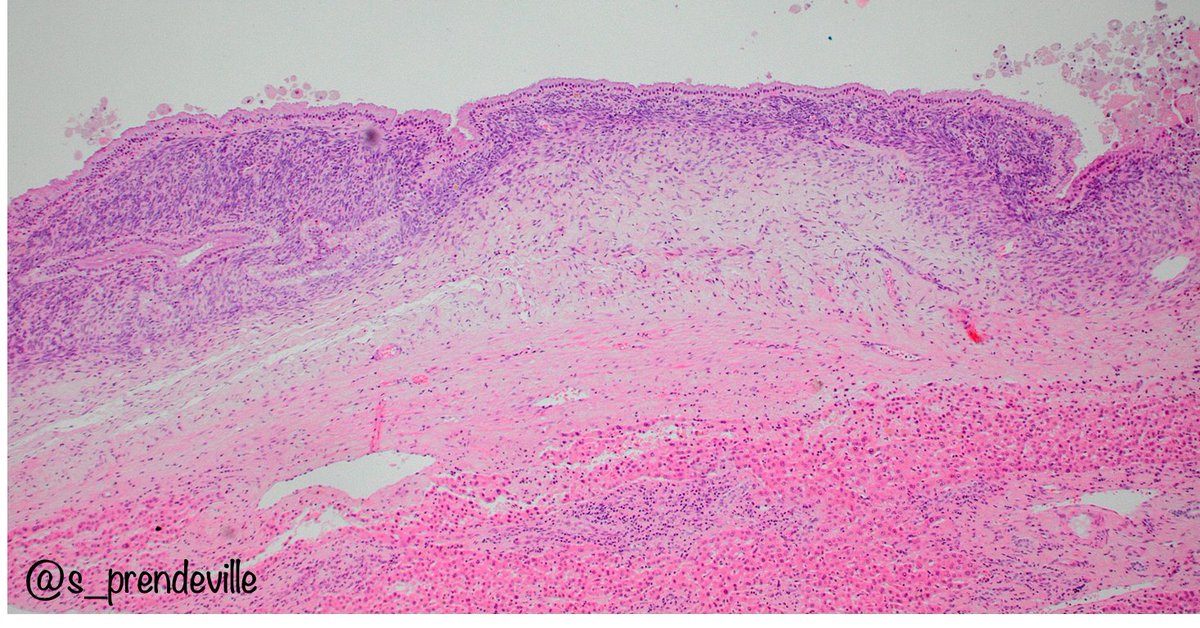

Happy to share our work with @OwkinScience on a daring challenge: Can #PDAC epithelial and stromal molecular phenotypes be identified from standard histology slides? Better yet, can this help resolve intra-tumor heterogeneity? a thread 🧵 nature.com/articles/s4146…